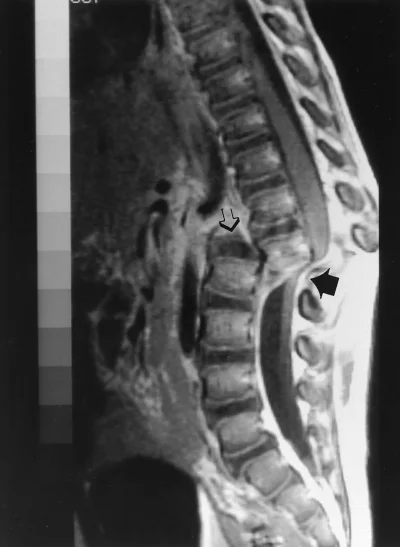

Noista kuvista tuli mieleen että eikös se yks italialainen(?) seppä suunnitellut tekevänsä ihmiselle päänsiirron? Missähän vaiheessa se rojekti.